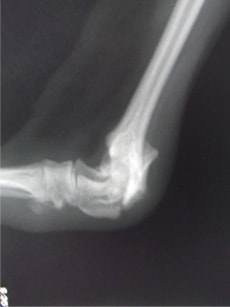

ペルシャ猫 11ヶ月齢 雄

他院にて左大腿骨遠位の成長板骨折(salter-harrisⅠ型)が認められており、治療相談を目的として来院。当院にて、キルシュナーワイヤーを用いたピンニングにより骨折部位の整復を行いました。術後の経過は良好で、現在も経過観察中です。

術前レントゲン